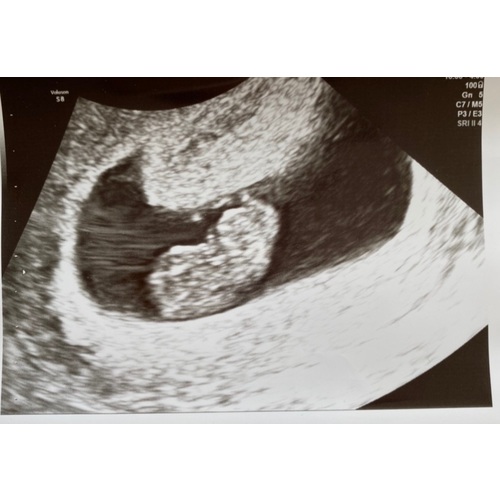

8 weken❤️

Inwendig! 8+1